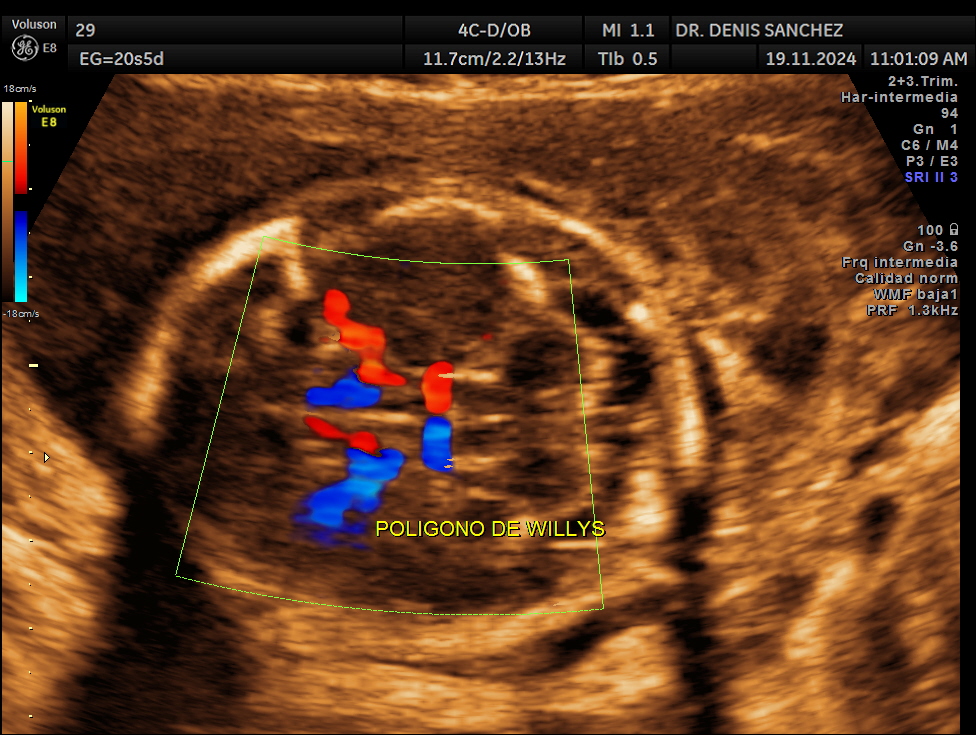

Ecografía Doppler fetal del segundo trimestre realizada por el Dr. Denis Sánchez en Quito, mostrando el polígono de Willis y la irrigación cerebral durante el estudio anatómico o morfológico del bebé.